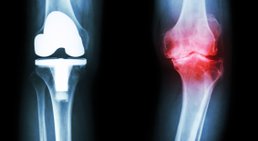

Als Facharzt für Orthopädie und Orthopädische Chirurgie habe ich mich auf die Behandlung von Verletzungen und Erkrankungen des Fußes, des Knies und der Hüfte spezialisiert.

Knieprothese